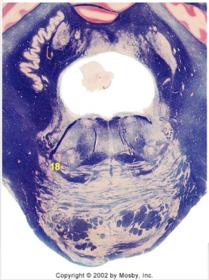

| Medullary pyramids | |

| Hypoglossal nucleus | |

| Hypoglossal nerve | |

| Dorsal motor nucleus of X | |

| Nucleus ambiguus | |

| Solitary tract | |

| Solitary nucleus | |

| ALS | |

| Medial lemniscus | |

| Medial longitudinal fasciculus | |

| Spinal tract of V | |

| Spinal nucleus of V | |

| Lateral (external, accessory) cuneate nucleus | |

| Anterior spinocerebellar tract | |

| CN IX | |

| Inferior cerebellar peduncle | |

| Inferior olivary complex | |

| Dorsal cochlear nucleus | |

| Inferior vestibular nucleus | |

| Medial vestibular nucleus | |